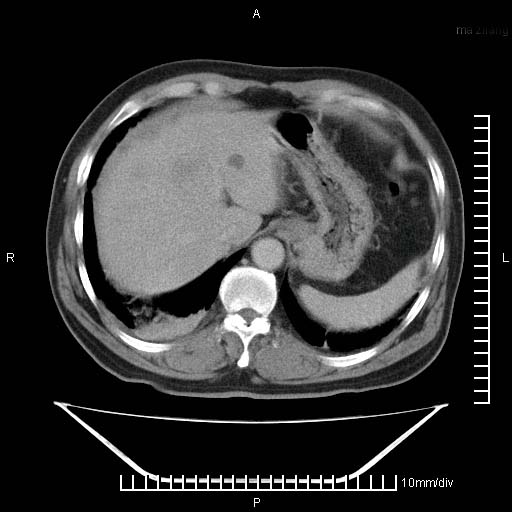

标题: CT25082:肝脏增强:男性,70岁 [打印本页]

标题: CT25082:肝脏增强:男性,70岁

患者以心脏疾病收住院,腹部无明显症状,b超查肝脏有占位。

增强效果不理想。考虑转移,胆囊壁明显增厚,不排除胆囊癌肝转移。

病灶无强化,考虑囊肿。

牛眼征,中心坏死无强化,外缘强化,最外缘又见低密度,考虑转移,与脓肿鉴别

肝内多发转移瘤,右下肺炎症并少量胸水。胃壁增厚建议胃镜,胰尾部“病变”为肠管。

1)肝脏多发性转移瘤(不排除胰尾癌转移所致可能)。2)腹水。3)右侧少量胸腔积液。

ct25082 结果:转移瘤

外院mr结果:胰尾恶性占位。